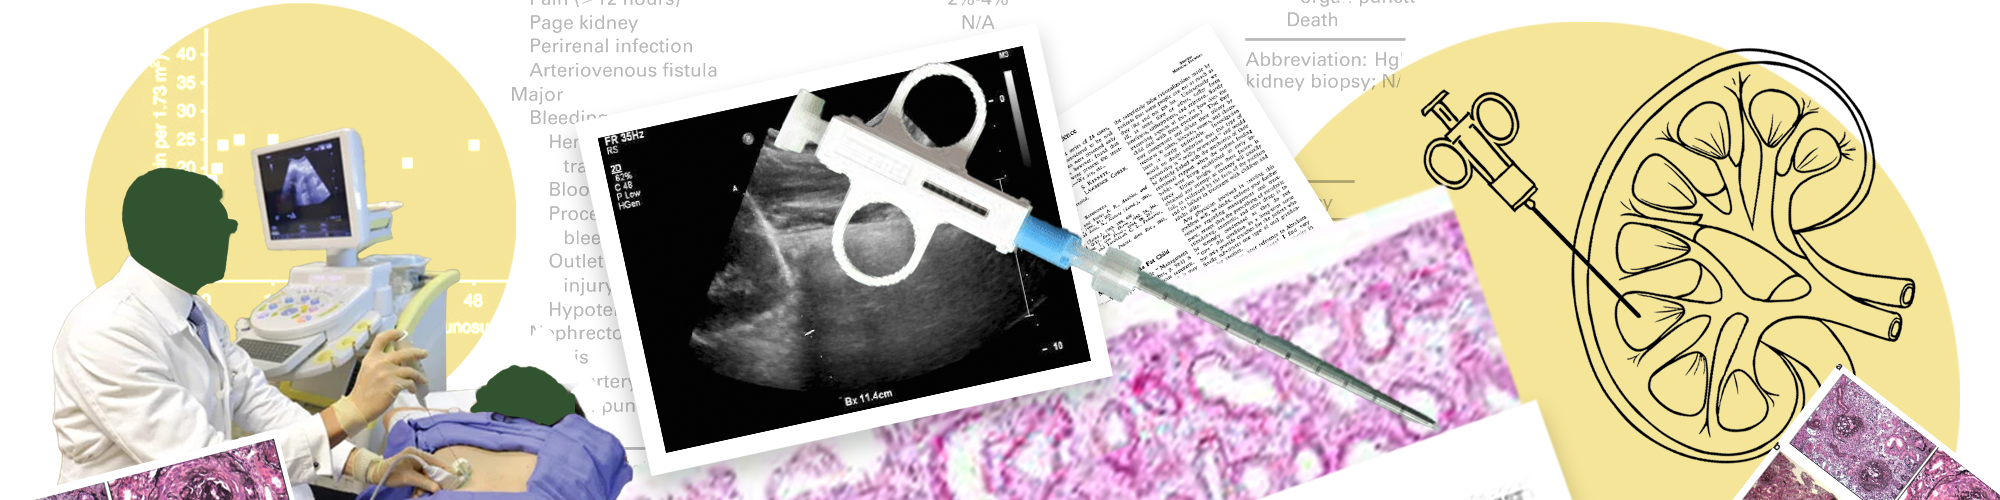

Most often, a doctor performs a kidney biopsy by inserting a thin needle through the skin. This is called a percutaneous kidney biopsy. An imaging device helps the doctor guide the needle into the kidney to remove tissue.

• With an ultrasound probe, your doctor identifies exactly where to insert the needle. In some cases, a CT scan may be used instead of ultrasound.

• Your doctor makes a small incision where the needle will go in and uses the ultrasound device to guide the needle into your kidney.

• You may be asked to hold your breath as your doctor collects a sample using a spring-loaded instrument. You may feel a "pop" or pressure and hear a sharp clicking noise.

Your kidney tissue goes to a lab to be examined by a doctor who specializes in diagnosing disease (pathologist). The pathologist uses microscopes and dyes to look for unusual deposits, scarring, infection or other abnormalities in the kidney tissue.